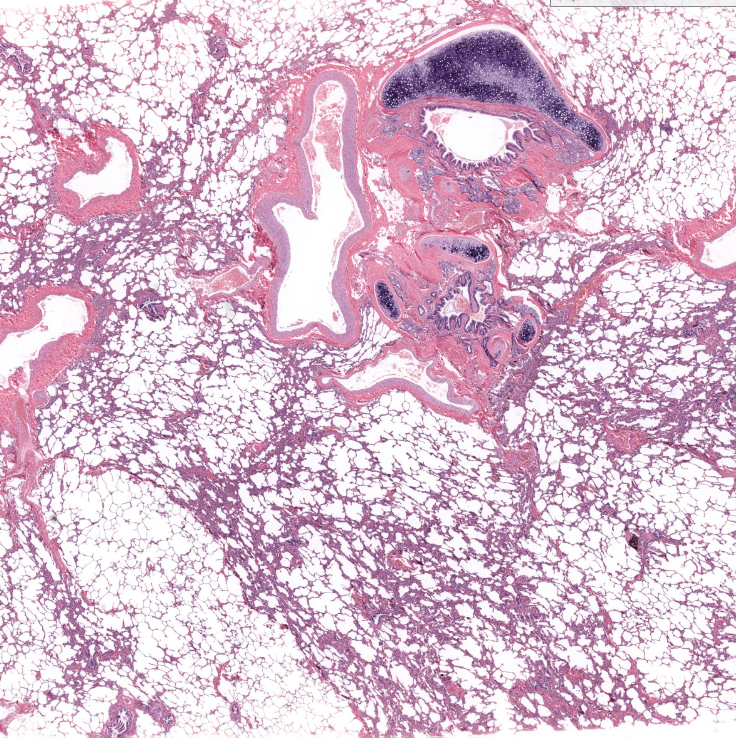

(organ)

lung

bronchiole cartilage of lung

terminal bronchiole of lung